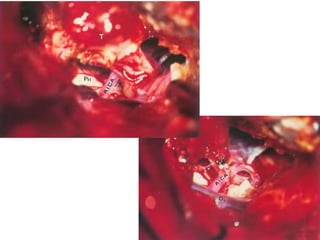

After the attached muscles have been dissected away, the

styloid process (SP) is fractured using a rongeur. FC Fallopian canal,

FN Facial nerve, FN(p) Rerouted part of the intraparotid facial nerve,

TB Temporal bone

Fig. 9.21 To obtain control over the vascular structures as they enter

the temporal bone, the tympanic bone (TB), the fallopian canal remnants

(FC), and the infralabyrinthine air cells are all to be removed.

C Basal turn of the cochlea (promontory), IJV Internal jugular vein,

JB Jugular bulb, SS Sigmoid sinus

The view after completely uncovering the lateral surfaces of

the vascular structures. C Basal turn of the cochlea (promontory), ICA

Internal

carotid artery, IJV Internal jugular vein, JB Jugular bulb, SS Sigmoid

sinus